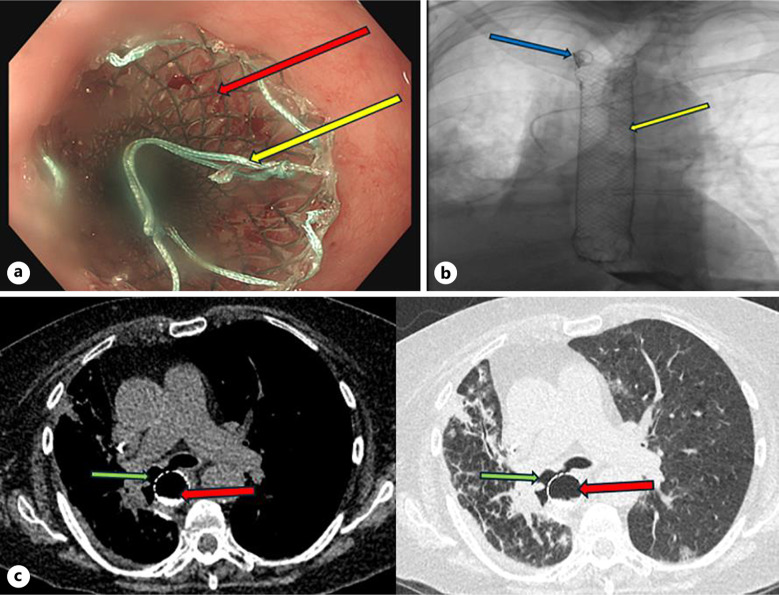

Case presentation: This report discusses the case of a 71-year-old female who presented with shortness of breath and a continuous cough secondary to a fistula between the oesophagus and right bronchus on the background of squamous cell carcinoma (SCC). This patient was seen by oncologists for the treatment of her lung cancer after right middle and lower lobe lobotomies, which was then treated with radiotherapy. On admission, a computed tomography scan revealed that the patient had a BOF due to therapeutic radiotherapy for SCC. She underwent intervention from the gastrointestinal and respiratory physicians to treat the BOF. Oesophageal stent placement was performed for treatment; however, the BOF remained patent, so a bronchial stent was considered for insertion. While the patient was awaiting the bronchial stent, she died.